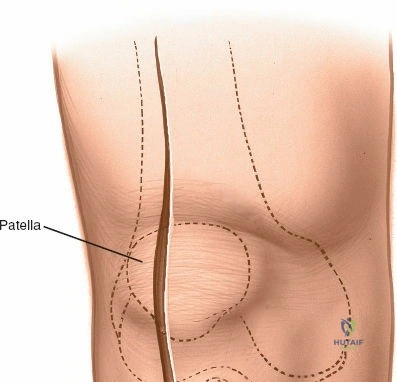

1. Skin Incision

The incision typically begins approximately 3-5 cm proximal to the superior pole of the patella, curves slightly medially along the patellar border, and extends distally parallel to the medial border of the patellar tendon, terminating approximately 2-3 cm distal to the tibial tubercle. A straight midline longitudinal incision is an alternative, particularly when combined with a medial parapatellar capsular approach for TKA, offering a large exposure. The length and curvature of the incision are tailored to the specific procedure and patient anatomy.

Initial skin incision marked, extending proximally along the quadriceps, medially to the patella, and distally along the patellar tendon.

2. Subcutaneous Dissection

- The skin and subcutaneous tissues are incised.

- Careful dissection is performed to identify and protect the infrapatellar branch of the saphenous nerve. This nerve typically courses obliquely across the anterior knee, often near the distal extent of the patella or patellar tendon. It lies within the subcutaneous fat and should be identified and carefully retracted, ideally preserved intact, to minimize post-operative dysesthesia or neuroma formation.